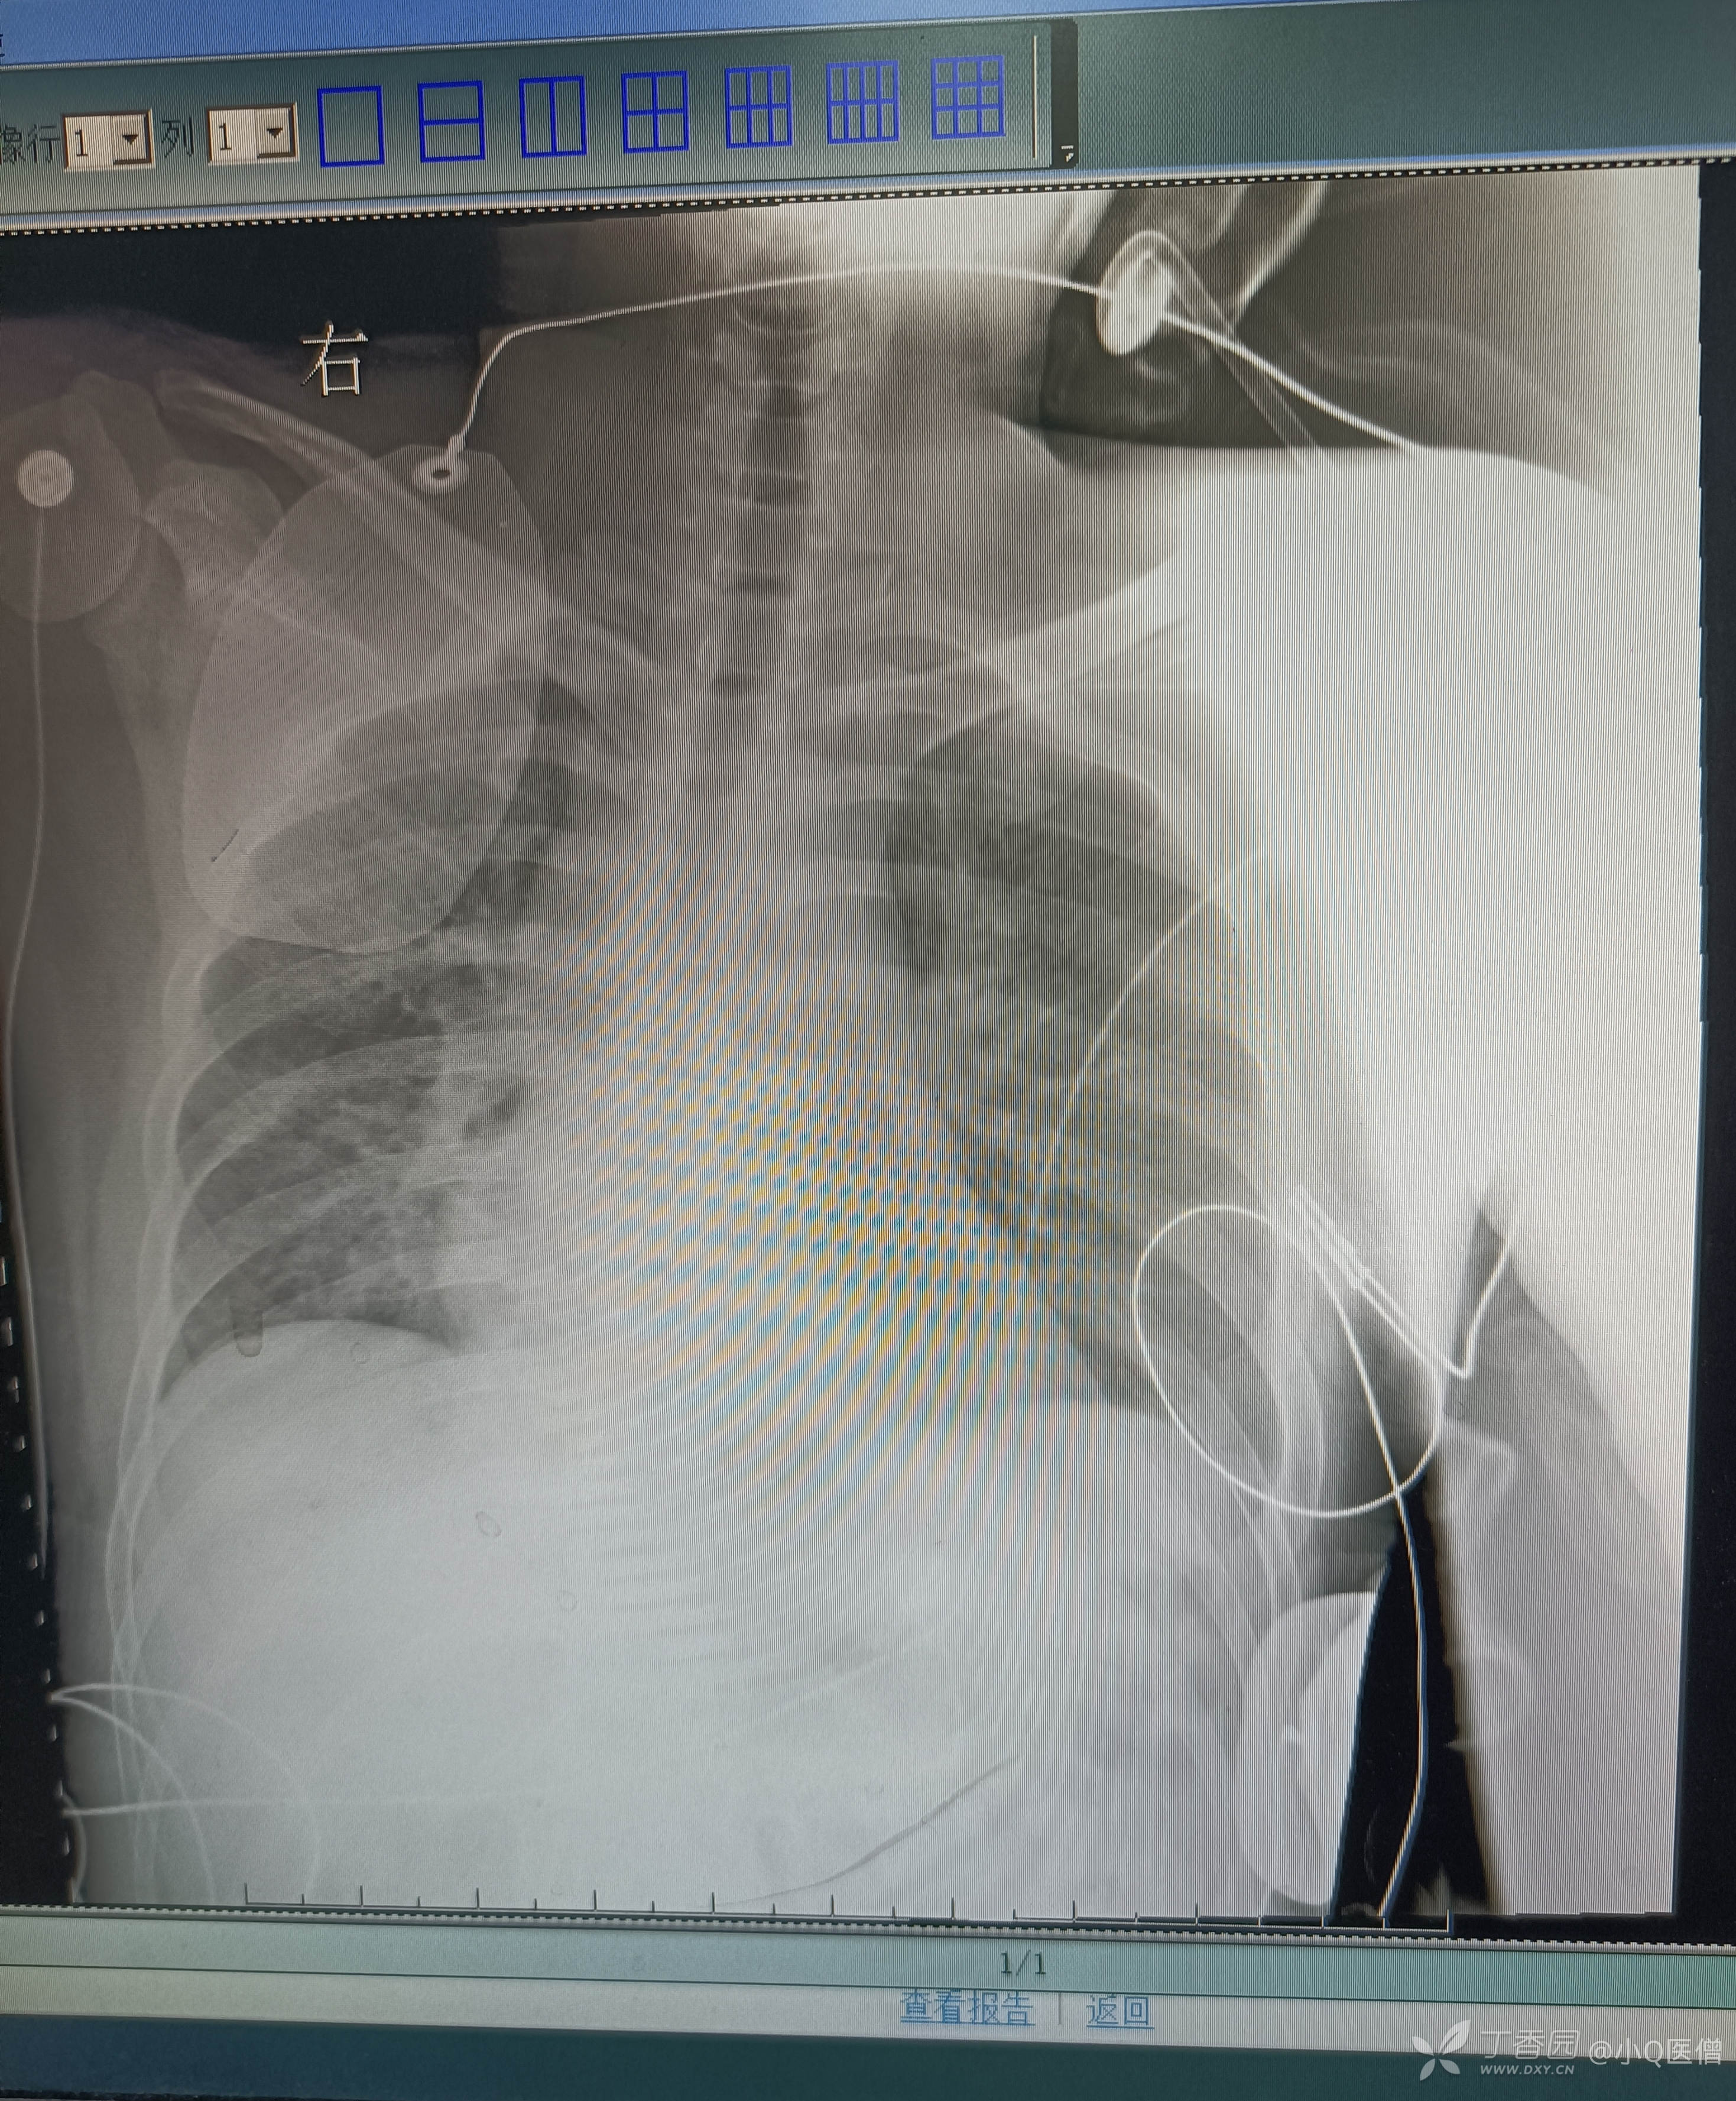

床旁胸片如下: